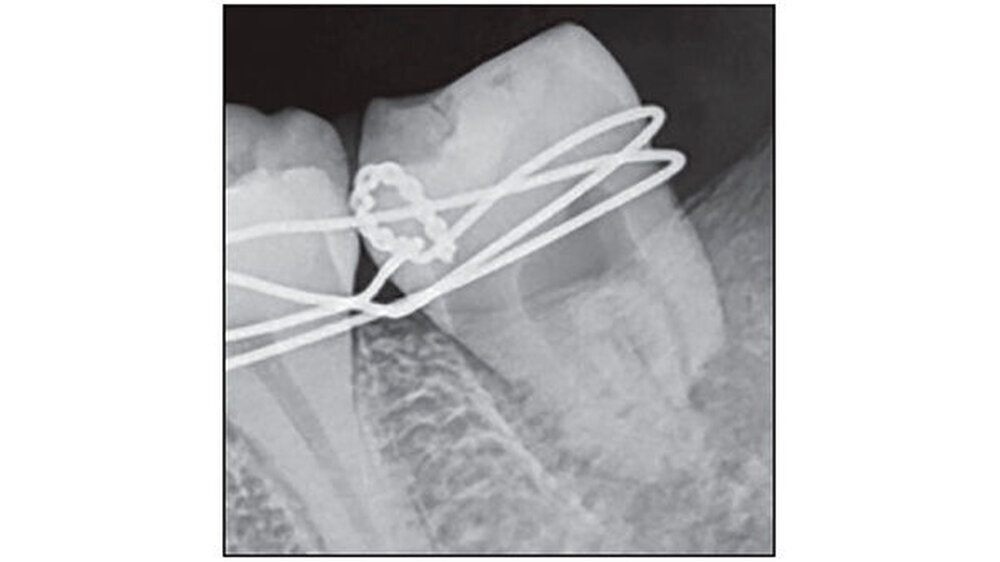

Zahn 38 wurde in das vorbereitete "Bett" von 37 transplantiert. Mit Nahtmaterial (Nähte India Pvt Ltd, Indien) stabilisierten die Zahnärzte die Position des transplantierten Zahns (Abbildung 3). Die intraradikuläre Schienung erfolgte mit formbarem kieferorthopädischem Draht (Tru-Bogen, Ormco Ltd., USA). Anhand eines postoperativen Röntgenbilds wurde die neue Position des 38 überprüft. Zur Unterstützung des Heilungsprozesses bekam die Patientin einen parodontalen Wundverband (Coe-Pack, G C Indien) angelegt.